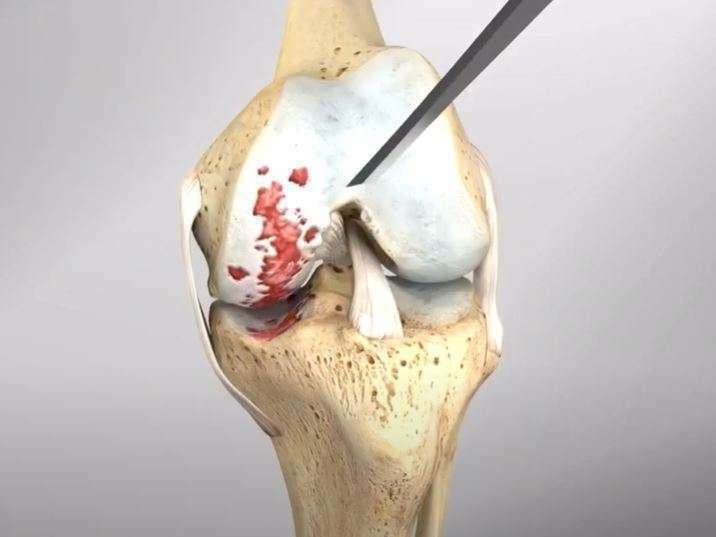

L’arthrose désigne un processus d’usure du cartilage liée au vieillissement. Ce n’est pas une fatalité liée à l’âge. Elle cause des dommages irréversibles du cartilage qui perd au fur et à mesure son rôle de surface de glissement et d’amortisseur. La pression sur l’os s’accroît à mesure que l’épaisseur cartilagineuse diminue.

Des excroissances osseuses, appelées ostéophytes, des kystes osseux et des ulcérations cartilagineuses se forment progressivement. En réponse, la membrane synoviale devient inflammatoire et produit un liquide synovial. L’excès de pression articulaire et l’inflammation sont les causent des douleurs de genou. La perte de congruence de l’articulation entraîne quant à elle, une diminution de la mobilité articulaire.